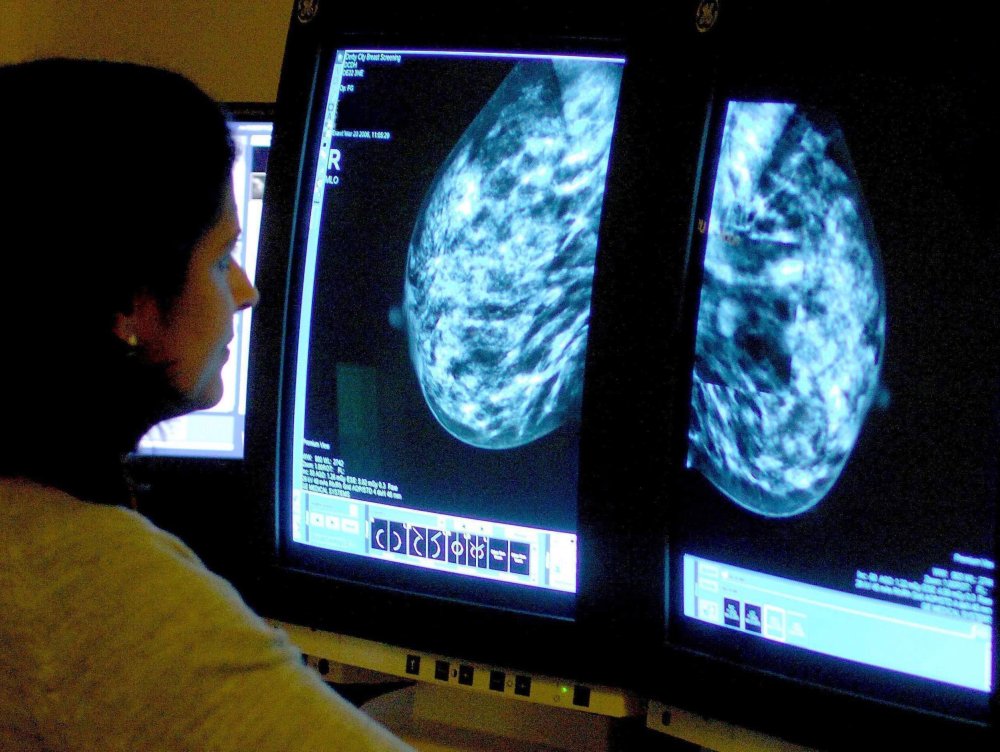

Imaging: Mammography

Your physician may suggest you get a mammogram, depending on your degree of risk, frequency of screening and age. Other types of imaging might be added, if an area of concern is spotted in the mammogram. If needed, a biopsy will be performed – which is the only way to know for sure if the suspicious area is cancer.